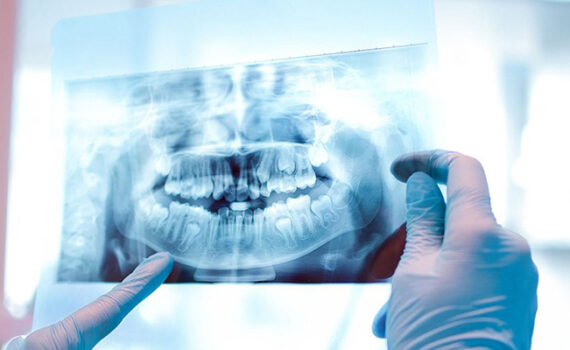

Наш центр визуализации предлагает полный спектр услуг по диагностической визуализации, включая рентген, МРТ, КТ, УЗИ, маммографию и ядерную медицину. Эти услуги визуализации играют важную роль в диагностике и мониторинге широкого спектра заболеваний.

Мы используем самые современные технологии и оборудование в наших лабораториях и службах визуализации. К ним относятся передовые системы визуализации и автоматизированные лабораторные приборы, обеспечивающие высокие стандарты точности диагностики.